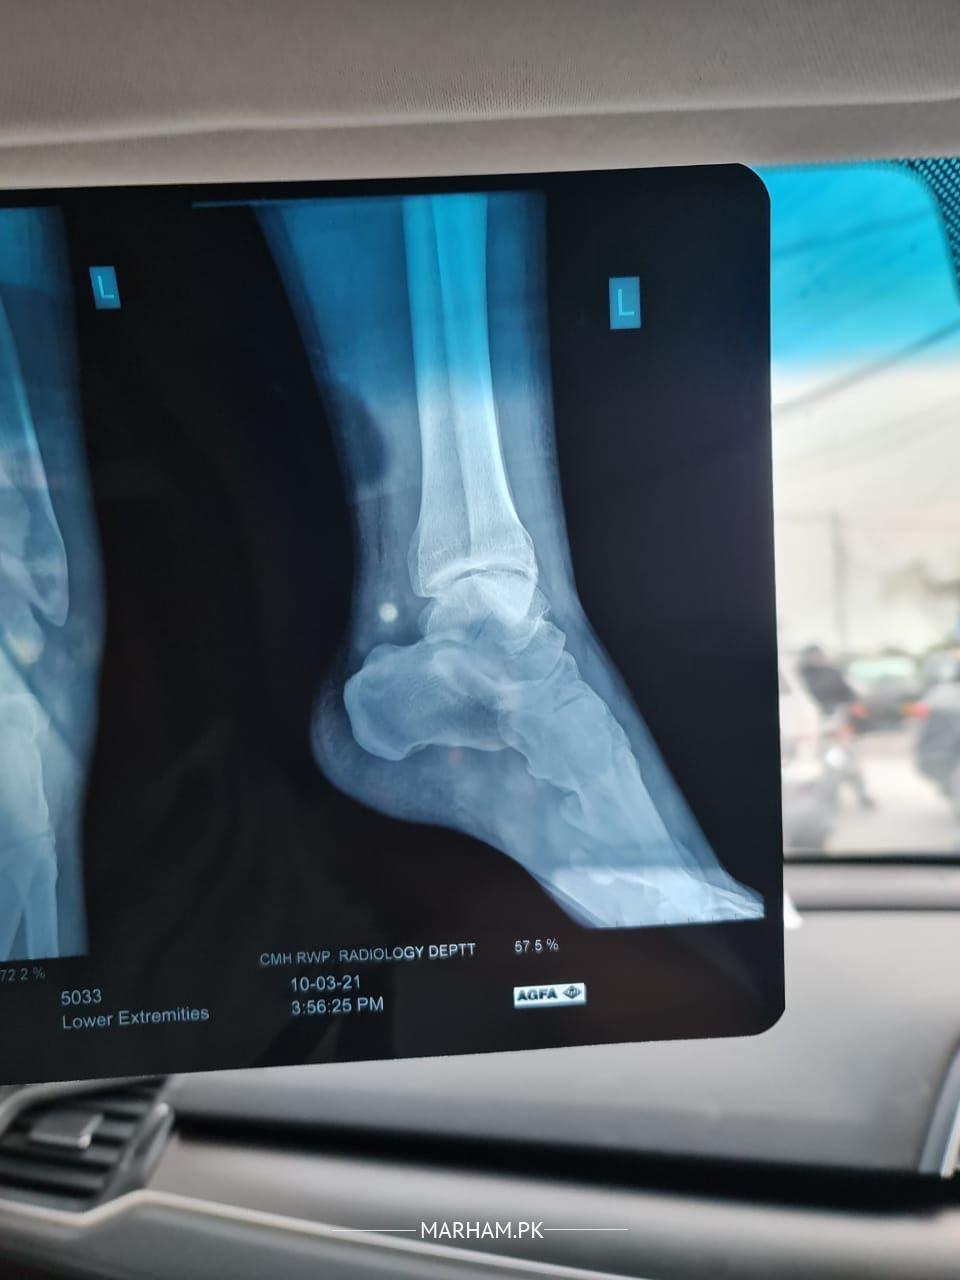

My husband fell down from stairs and had a fracture in his talus bone. The doctors are saying that we need to operate it and insert screws to fix the bone that has been cracked and dislocated. Can it be fixed without operation only with plaster. Xray has been attached kindly advise